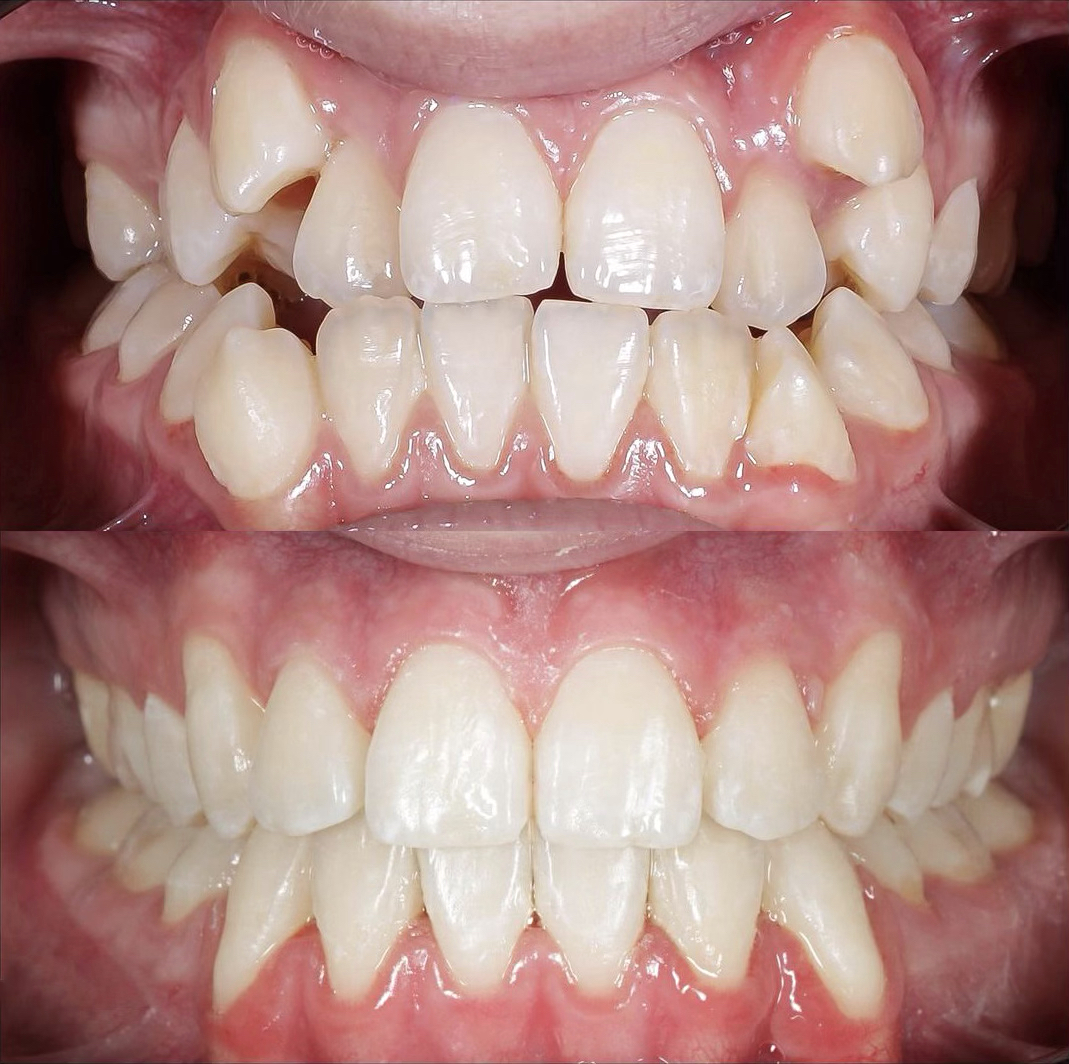

Произведена комплексная эстетическая реабилитация улыбки. Восстановлены правильные пропорции зубов, улучшено цвет и форму, гармонизирована улыбка с чертами лица. Сохранен максимальный объем собственных тканей — достигнут естественный и гармоничный результат.

Произведено: диагностику, цифровую планировку улыбки, моделирование формы зубов, минимально инвазивную подготовку, установку керамических реставраций E-max. Результат: гармоничная форма зубов, естественный цвет и прозрачность, правильная длина резцов, более открытая и выразительная улыбка с сохранением собственных тканей зуба.